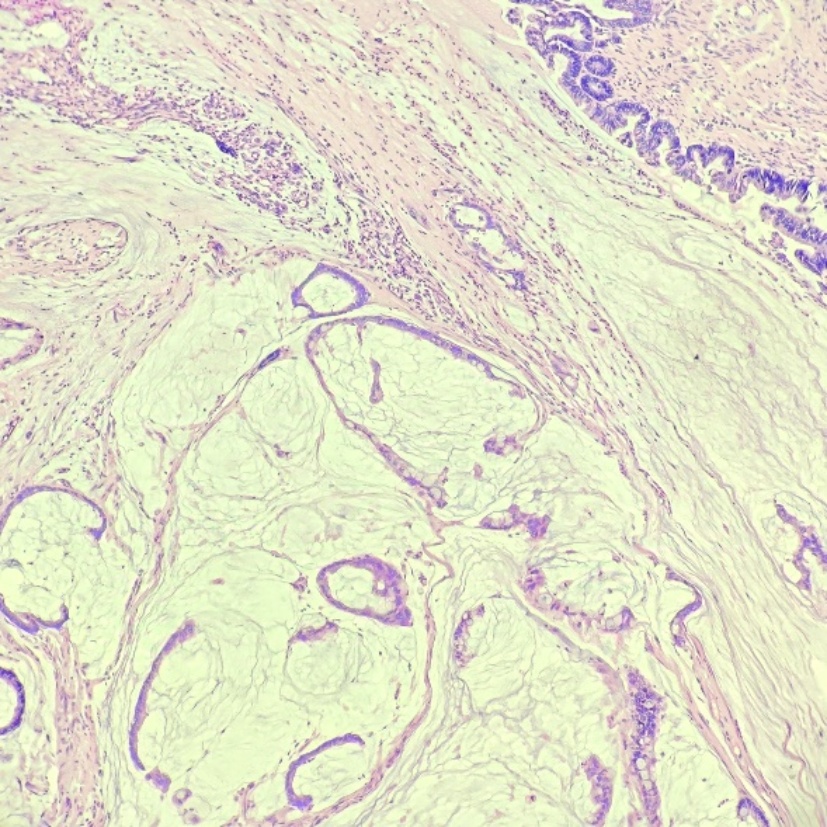

患者,女,56岁。2024年3月因“间断右下腹痛1月余”就医。患者1月余前无明显诱因开始出现右下腹痛,呈阵发性钝痛,无恶心、呕吐,无腹胀、腹泻,无畏寒、发热,无呕血、黑便,行B超示:右下腹阑尾区不均质低回声团,阑尾炎可能性大,给予对症抗感染治疗,症状有所缓解,但仍反复疼痛,为求进一步治疗收入当地医院。既往有高血压病史,16年前因肠套叠行结肠切除手术。查体:心肺检查未见明显异常,腹部平坦,无腹壁静脉曲张,腹部可见陈旧手术瘢痕,腹软,右下腹压痛,无反跳痛及肌紧张,腹部未触及明显肿块,叩诊呈清音,移动性浊音阴性,肠鸣音3次/分,未闻及血管杂音。入院后完善血常规:白细胞6.61*10^9/L (3.5~9.5)、消化系统肿瘤标记物:癌胚抗原2.4 ng/ml (13~150),甲胎蛋白3.87 ng/ml (≤7),类抗原19-9 31.9 ng/ml (≤34)均正常。腹部CT示:腹腔内部分小肠积液。右下腹局部见管状影,壁钙化。回盲部见多发微小结节,乙状结肠内见高密度灶(见图1(a)~(d))。肠镜示:回盲瓣呈唇状,阑尾肿大,开口处黏膜粗糙糜烂,蠕动可(见图2)。给予行腹腔镜下阑尾切除术,术中探查见:阑尾端侧与临近小肠致密黏连,无法分离,完整切除阑尾困难,为避免损伤黏连小肠,剪刀贴近黏连处将阑尾浆膜剪开,剥离阑尾,部分浆膜残留于小肠,距离阑尾根部0.5 cm结扎,切除阑尾。术后病理:送检破碎阑尾组织,部分管腔上皮呈高级别上皮内瘤变,少量破碎游离组织内见数个异型腺体浸润性生长,考虑癌变,高分化腺癌。组织碎,浸润层次不明确,阑尾肌层及浆膜层见多量无细胞黏液及炎症反应(见图3(a)图3(b))。患者术后5天顺利出院。

(a) (b)

(c) (d)

Figure 1. Abdominal CT (Before the first surgery)

1. 腹部CT(第一次手术前)